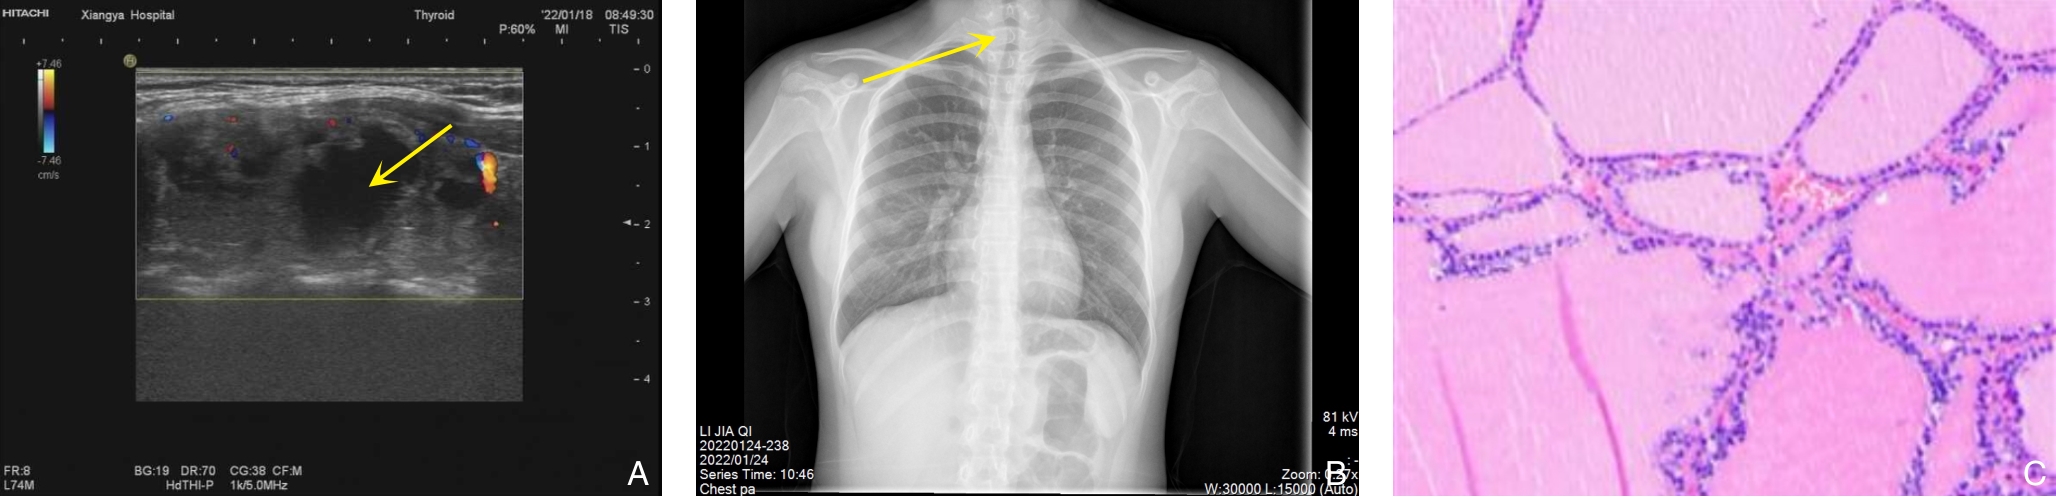

背景与目的 DICER1综合征是一种由DICER1基因胚系突变引起的罕见常染色体显性遗传性肿瘤易感综合征,可累及多器官并表现为多种良恶性肿瘤或增生性病变。肾外肾母细胞瘤、多结节性甲状腺肿及Sertoli-Leydig(S-L)细胞瘤均为其相关表型,但三者同时出现的病例尚未见报道。本文报告1例同时合并上述三种表型的DICER1综合征患者,并结合文献进行分析,以提高对该综合征复杂临床谱系的认识。方法 回顾性分析1例女性患者的临床资料,包括临床表现、影像学检查、手术经过、病理学及免疫组化结果、基因检测及家庭谱系图分析结果;同时检索并总结近30年相关文献,对具有肾母细胞瘤、结节性甲状腺肿及S-L细胞瘤等表型的DICER1综合征病例进行归纳分析。结果 患者9岁时因腹痛行右侧卵巢肿瘤切除术,病理诊断为原发性卵巢畸胎样肾外肾母细胞瘤,术后行辅助化疗。3年后因甲状腺结节行右侧甲状腺切除术,病理为多结节性甲状腺肿。半年后因左侧盆腔新发肿块行卵巢囊肿剥除术,病理提示低分化S-L细胞瘤。基因检测发现DICER1基因外显子8 c.904-1G>C杂合突变,其父亲为同位点杂合突变携带者。结合临床表现及分子遗传学结果,确诊为DICER1综合征。随访3年未见复发或新发病灶。文献复习显示,同时合并上述三种表型的病例尚未见报道。结论 DICER1综合征临床表型多样且诊断具有挑战性。当患儿出现多器官肿瘤或罕见肿瘤组合时,应警惕遗传性肿瘤综合征的可能,尽早开展基因检测及家系筛查。早期识别DICER1综合征对于制定个体化治疗策略及开展长期监测随访具有重要意义。